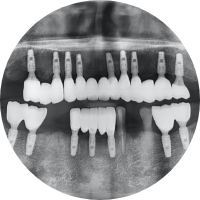

상실된 치아를 위해 목포미르치과병원에서는 컴퓨터 분석 시스템을 활용하여

개인의 구강 구조를 면밀히 파악하고,

환자의 심미성과 기능성을 모두 만족하는 맞춤형 임플란트를 제공합니다.